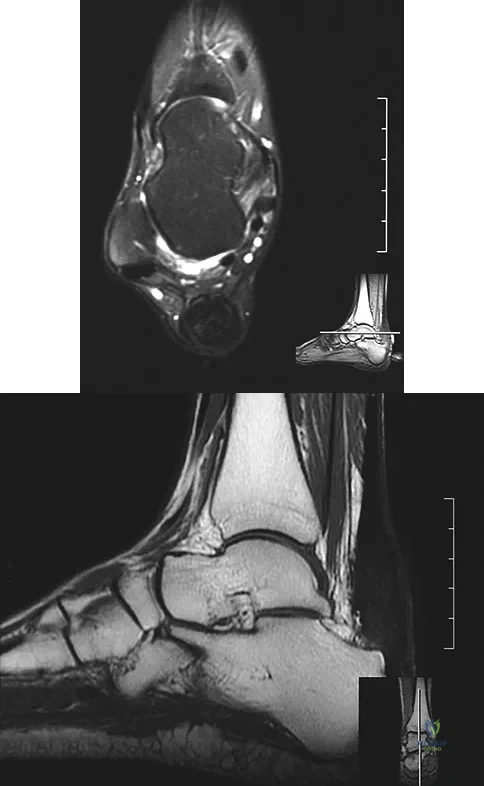

A 58-year-old woman with rheumatoid arthritis and a severe hindfoot valgus deformity now reports recurrent lateral ankle pain. Examination reveals pain over the fibula and sinus tarsi, with a valgus hindfoot that is passively correctable. Despite the use of an ankle-foot orthosis, this is the second time this problem has occurred. Radiographs and a clinical photograph are shown in Figures 28a through 28c. What is the next most appropriate step in treatment?

Explanation